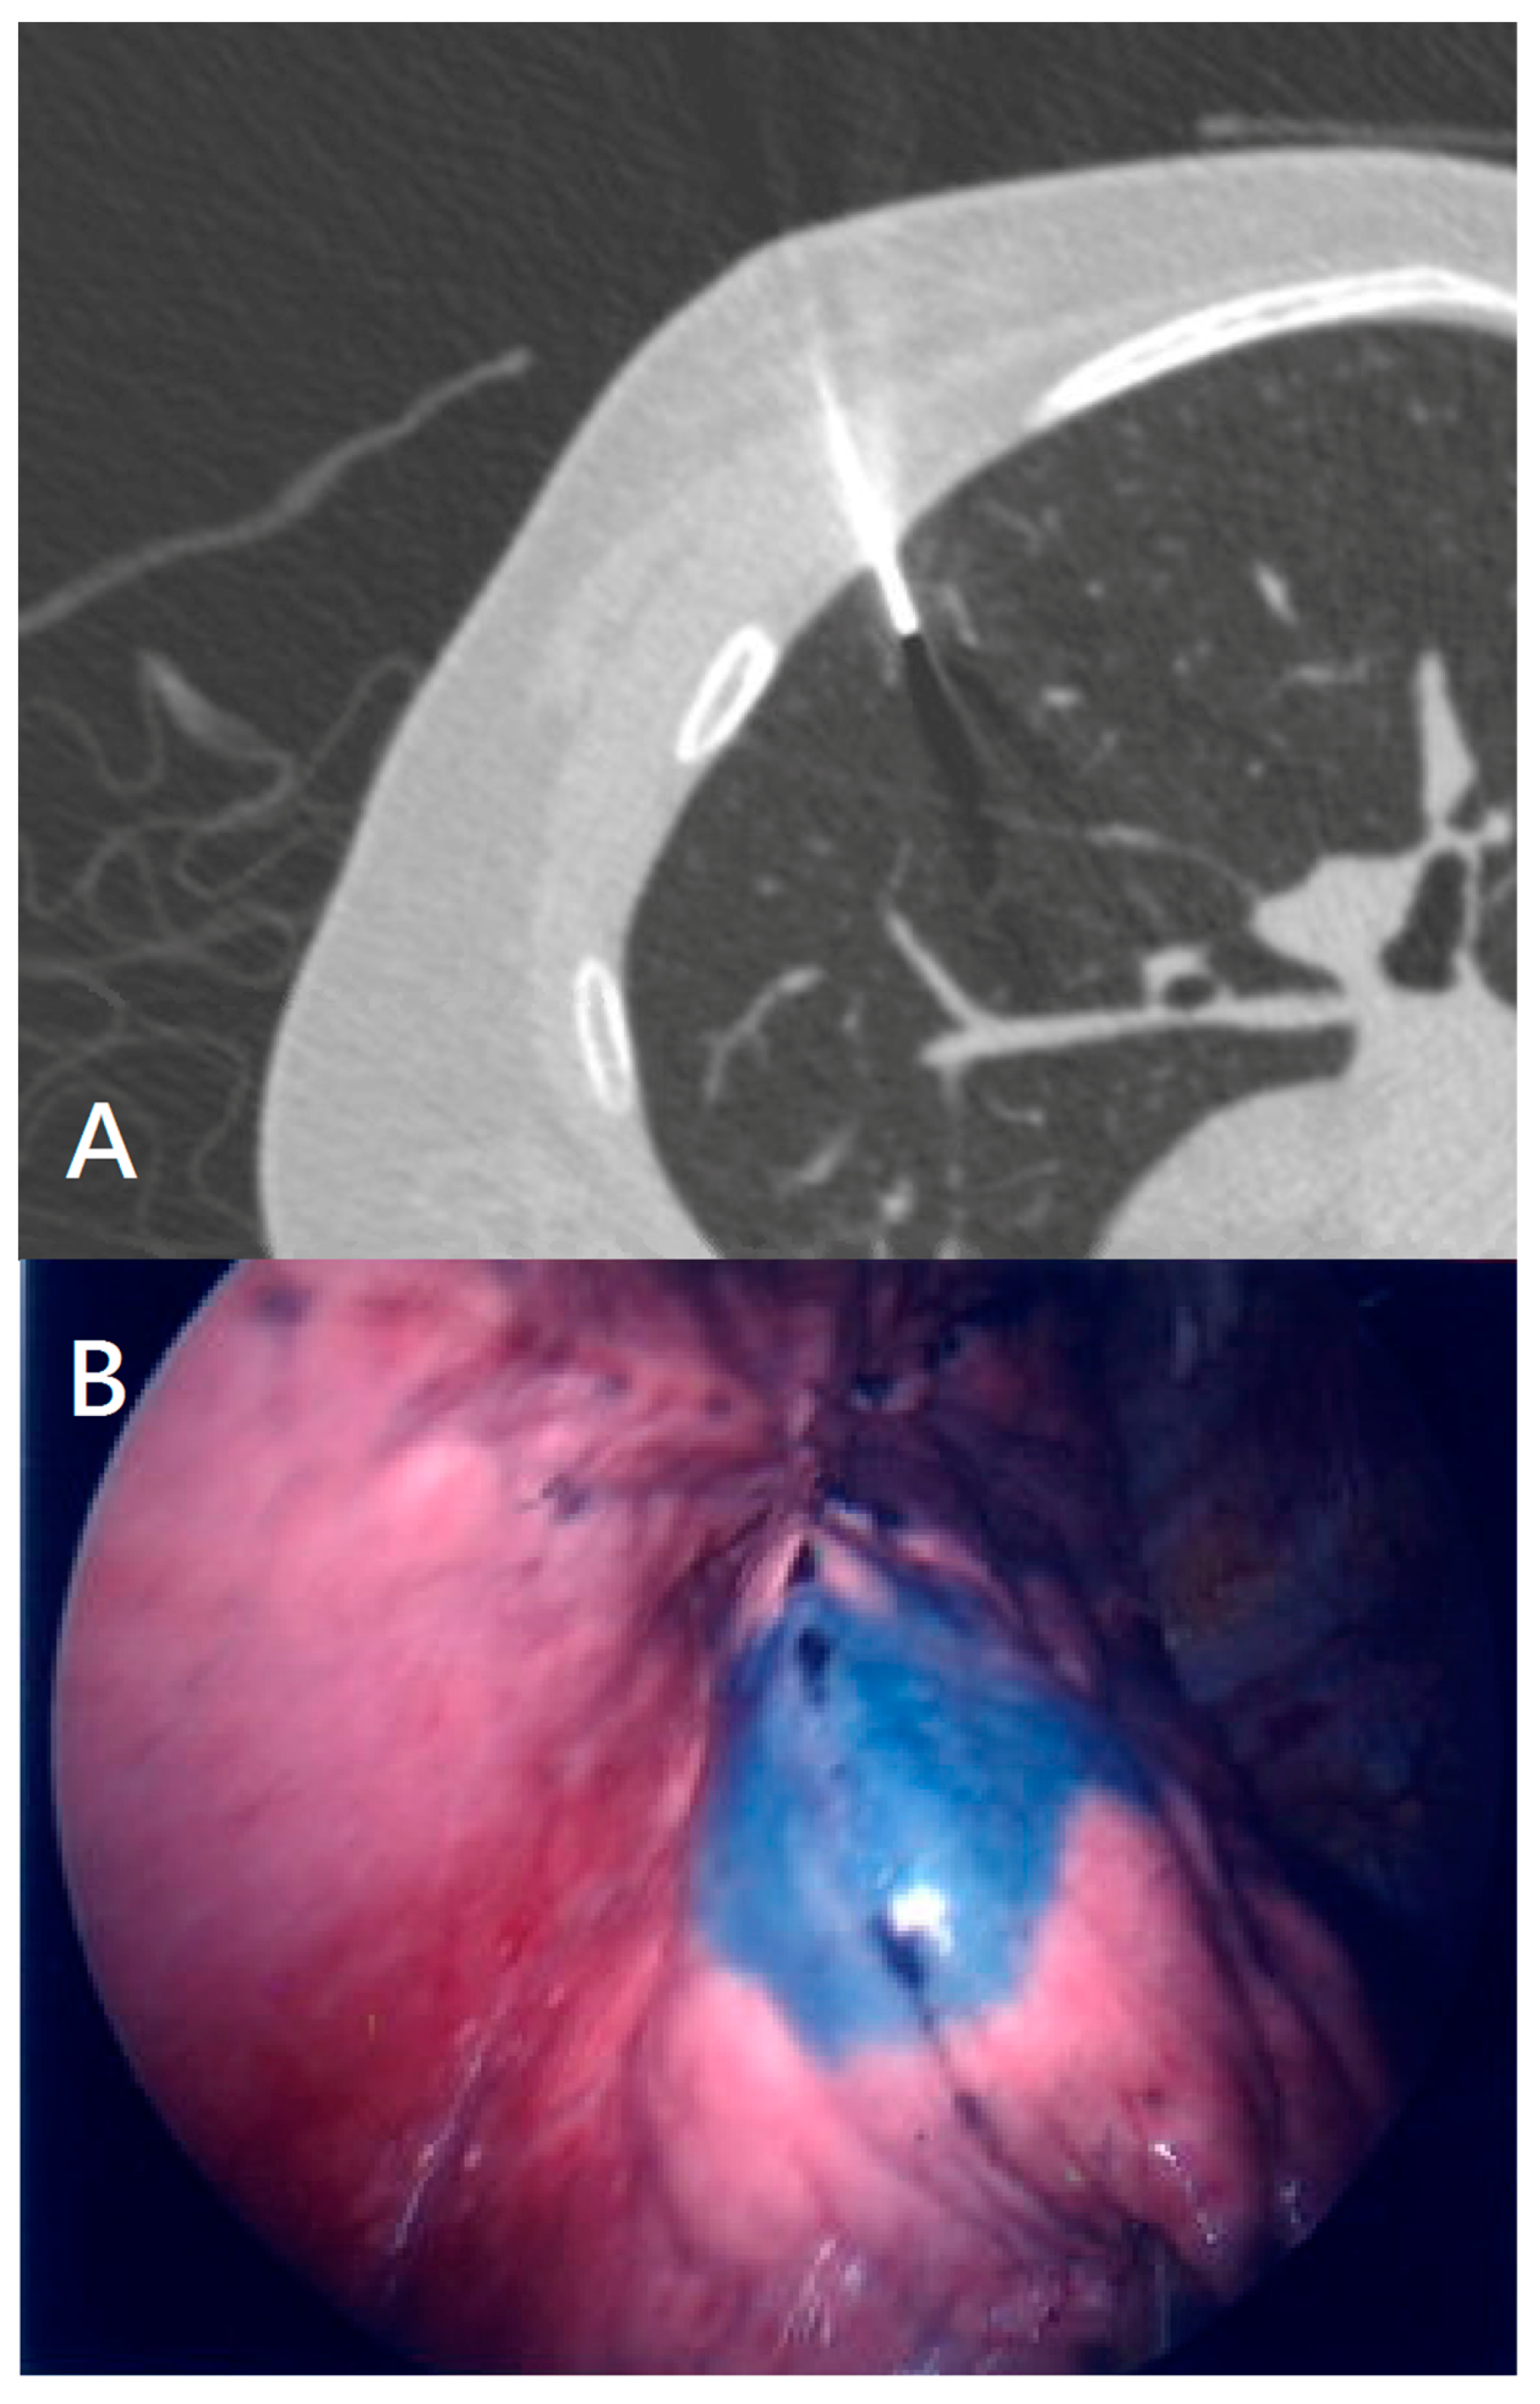

Electromagnetic Navigation Bronchoscopy Localization versus Percutaneous CT-Guided Localization for Lung Resection via Video-Assisted Thoracoscopic Surgery: A Propensity-Matched Study